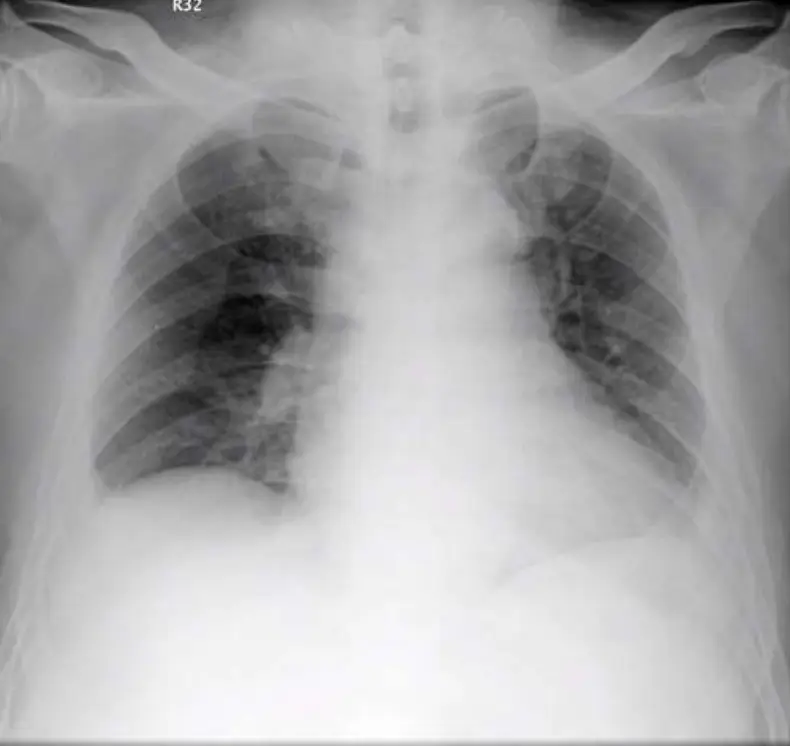

病人,64歲傅先生在下午3:00 PM 突然氣促(dyspnea),到急診求醫。病人有高血壓、慢性B型肝炎及痛風病史。到院時血壓102/73mm Hg; ventricular rate 100/min;在10 L/min O₂ mask 使用下SpO₂ 100%。在急診之身體檢查末見重大異常。其心電圖及CxR如圖。靜脈血氧氣及生化檢查如表,超音波心圖顯示右心擴大及中重度三尖瓣閉鎖不全。本病人之診斷及治療之緊急處置,以何方案最適當?

- 胸部X光:右肺野顯示血管紋理減少(oligemia,Westermark sign)及右下肺靠近胸膜處見弧形楔狀透明度減少區(Hampton’s hump),同時主肺動脈影像稍增寬(Fleischner sign),高度支持肺栓塞診斷。